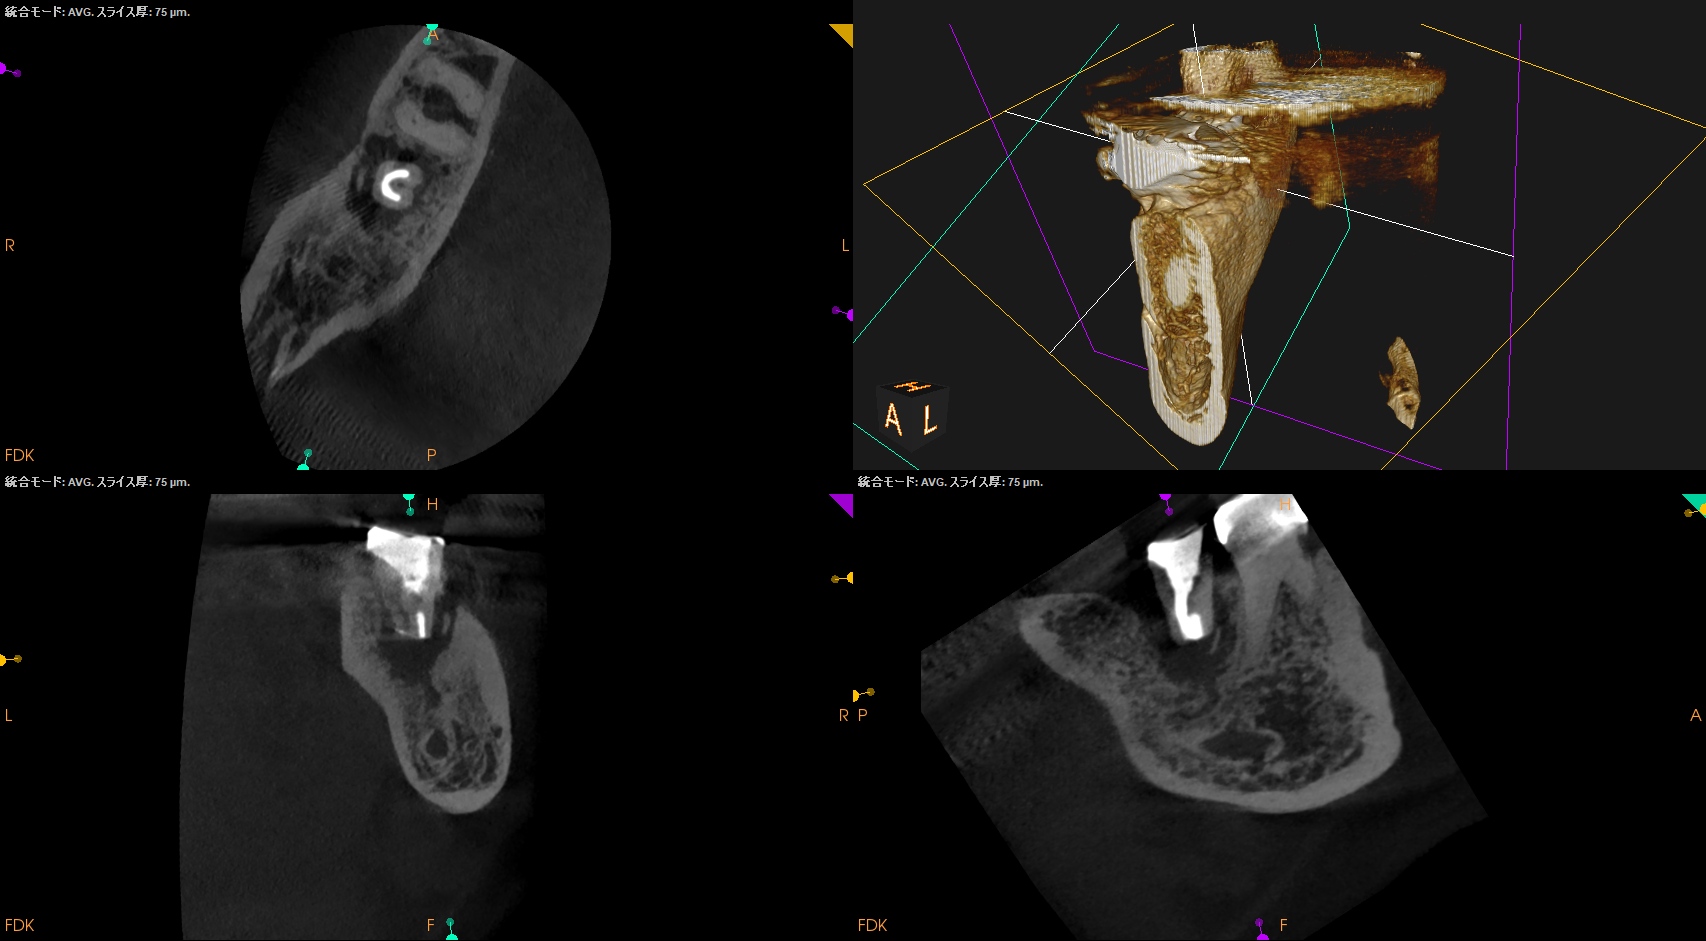

PA, CBCTを撮影した。

ML

MB

D

問題はないだろう。

この歯牙の根尖部の歯槽骨が回復するかどうか?は時間が解決する。